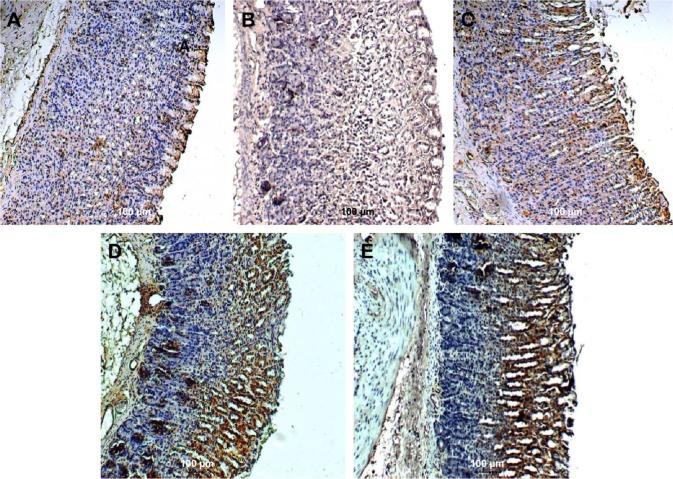

Clausena excavata is a natural herb with both antioxidant and anti-inflammatory properties. It has been used for decades in folkloric practice for the amelioration of various ailments. In this study, the gastroprotective activity of methanolic extract of C. excavata leaves (MECE) was determined in the Sprague Dawley rat ethanol-induced gastric ulcer model. Rats were pretreated with a single dose of vehicle (5% Tween 20), 20 mg/mL omeprazole, 400 and 200 mg/mL of MECE dissolved in 5% Tween 20. Ulcer was induced with 5 mL/kg of ethanol and stomach tissue was obtained after 1 hour. Histological examination was done on hematoxylin and eosin, periodic acid-Schiff, and immunochemically stained gastric mucosal tissues. Prostaglandin E2, superoxide dismutase, catalase, glutathione peroxidase, and lipid peroxidation levels of the gastric tissue homogenates were also determined. Significantly (P<0.05) smaller ulcer areas, less intense edema, and fewer leukocytes' infiltration were observed in MECE- and omeprazole-treated than in untreated gastric mucosa with ulcer. The gastric pH, mucus production, superoxide dismutase, catalase, and glutathione peroxidase contents increased, while the lipid peroxidation content decreased as a result of MECE treatment. Bcl-2-associated X protein was underexpressed, while heat shock protein 70 and transforming growth factor-beta protein were overexpressed in the ulcerated gastric mucosa tissues treated with omeprazole and MECE. Similarly, there was a reduction in the levels of tumor necrotic factor-alpha and interleukin-6, while the level of interleukin-10 was increased. This study showed that the gastroprotective effect of MECE is achieved through inhibition of gastric juice secretion and ulcer lesion development, stimulation of mucus secretion, elevation of gastric pH, reduction of reactive oxygen species production, inhibition of apoptosis in the gastric mucosa, and modulation of inflammatory cytokines.

假黄皮是一种具有抗氧化和抗炎特性的天然草药。在民间实践中,它已被用于改善各种疾病数十年。在本研究中,在Sprague Dawley大鼠乙醇诱导的胃溃疡模型中测定了假黄皮叶甲醇提取物(MECE)的胃保护活性。大鼠分别用单剂量的赋形剂(5%吐温20)、20 mg/mL奥美拉唑、400和200 mg/mL溶解于5%吐温20中的MECE进行预处理。用5 mL/kg乙醇诱导溃疡,1小时后获取胃组织。对苏木精和伊红染色、过碘酸-希夫染色以及免疫化学染色的胃黏膜组织进行组织学检查。还测定了胃组织匀浆中前列腺素E2、超氧化物歧化酶、过氧化氢酶、谷胱甘肽过氧化物酶和脂质过氧化水平。与未治疗的溃疡胃黏膜相比,MECE和奥美拉唑治疗组的溃疡面积显著更小(P<0.05)、水肿程度更轻、白细胞浸润更少。MECE治疗后,胃pH值、黏液分泌、超氧化物歧化酶、过氧化氢酶和谷胱甘肽过氧化物酶含量增加,而脂质过氧化含量降低。在奥美拉唑和MECE治疗的溃疡胃黏膜组织中,Bcl-2相关X蛋白表达下调,而热休克蛋白70和转化生长因子-β蛋白表达上调。同样,肿瘤坏死因子-α和白细胞介素-6水平降低,而白细胞介素-10水平升高。本研究表明,MECE的胃保护作用是通过抑制胃液分泌和溃疡病变发展、刺激黏液分泌、提高胃pH值、减少活性氧产生、抑制胃黏膜细胞凋亡以及调节炎性细胞因子来实现的。